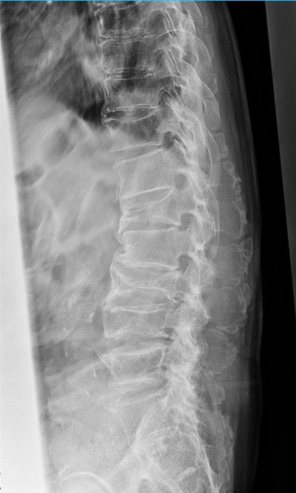

私たちの背骨(脊椎)は、横から見るとゆるやかなS字カーブを描いています。このカーブがあることで、体にかかる衝撃を分散し、無理なく体を支えることができます。

レントゲンで見る背骨の変化

腰痛の原因を調べる際には、単純レントゲン検査が行われることがあります。レントゲンでは骨の形や並び方を確認することができ、背骨の状態を客観的に見ることができます。

例えば、次のような変化が確認されることがあります。

レントゲン検査は短時間で行うことができ、腰痛の原因を探るための大切な手がかりとなります。ただし、腰痛の原因は筋肉や神経など骨以外にある場合もあるため、症状に応じて他の検査が行われることもあります。

腰痛の背景には、日常の姿勢や生活習慣が関係していることがあります。レントゲン検査では、背骨の並びや椎体の状態を確認することができ、腰痛の原因を調べる大切な手がかりになります。日頃から姿勢を意識し、適度な運動や休憩を取り入れながら、腰への負担を減らす生活を心がけましょう。気になる症状がある場合は早めに医療機関へご相談ください。